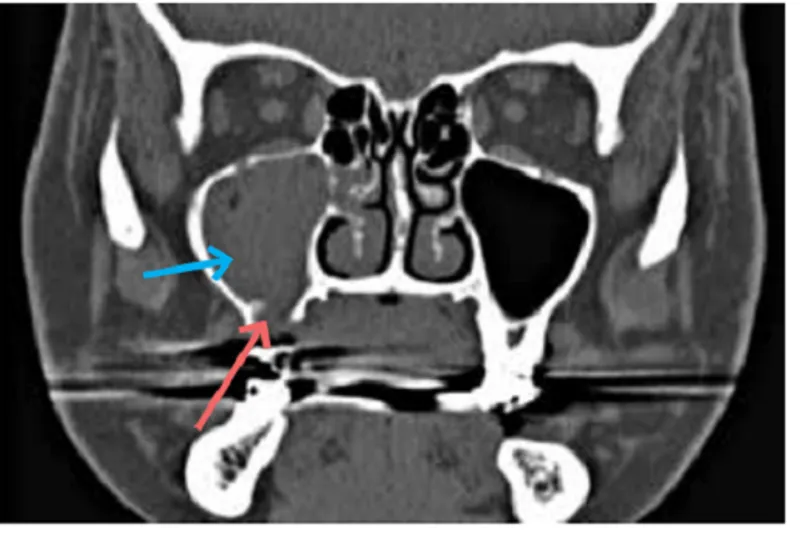

Der er ofte en tæt eller direkte anatomisk relation mellem bunden af sinus maksillaris og rodspidserne svarende til såvel præmolarer som molarer. Tandlæger bør derfor have kendskab til symptomer på kronisk sinuitis maksillaris med en odontogen årsag, herunder ætiologiske faktorer.

I alt blev 788 patienter identificeret med kronisk sinuitis maksillaris, hvor kirurgisk behandling blev foretaget. Prævalensen af en odontogen oprindelse var 37 (4,7 %) patienter. Der blev ikke identificeret tilfælde med bilateral sinuitis maksillaris i denne gruppe. Symptomerne havde persisteret i op til et år hos 67,5 % af patienterne ved første konsultation. Kronisk sinuitis maksillaris med en odontogen oprindelse var ofte associeret med tandekstraktion, rodfyldningsoverskud og apikal opklaring. Således var 59 % af tilfældene opstået i forbindelse med tandbehandling.